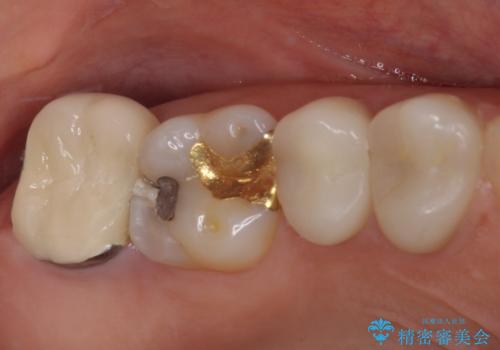

- 奥歯の間にものが挟まって不快であるとのことで来院された患者様です。

検査を行った結果、非常に強い咬合力により隣の歯との隣接面にひびが入り、虫歯が拡大している状態でした。

部分的にゴールドインレーが装着されていたので、虫歯と合わせて除去し、新たにゴールドインレーにて修復治療を行うこととしました。